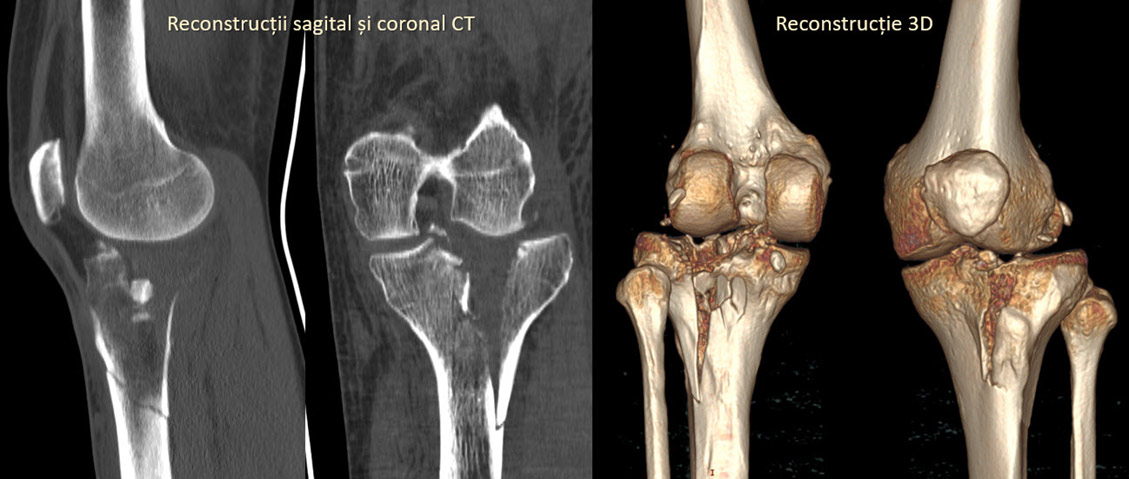

În cazul unui afecțiuni traumatice, cu leziune aparentă sau nu pe radiografie, uneori se preferă computer tomografia, mai ales dacă ortopedul are nevoie de reconstrucția 3D a osului. Având în vedere însă că examinarea cu computer tomograful nu poate vizualiza corespunzător structurile ligamentare, tendinoase sau cartilajul, rezonanța magnetică este cea indicată în cele mai multe cazuri.

După achiziția inițială a imaginilor, pacientul poate să părăsească computer tomograful, urmând partea mai complicată de postprocesare. În această etapă se fac reformatări în toate planurile, atât coronal, cât și sagital și se analizeză imaginile atât în fereastra dedicată de os, cât și în fererastra dedicată țesutului moale. Se realizează reconstrucții 3D ale regiunii scanate, pentru o mai bună exemplificare a regiunii. Aceste proceduri postprocesare sunt deosebit de laborioase și de obicei sunt realizate de medicul radiolog sau de un operator foarte bine pregătit.